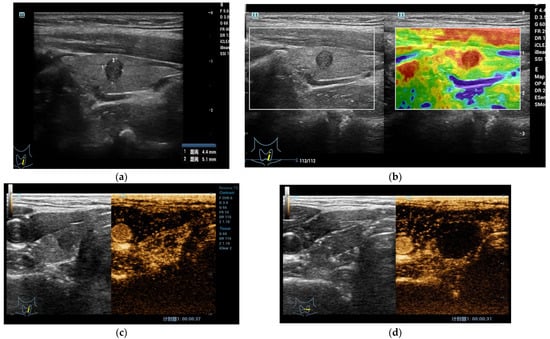

3.1. CEUS r in the Diagnosis of Thyroid Nodule

3.2. The Role of CEUS in the Evaluation of Thyroid Nodules after Thermal Ablation and Radioactive Iodine Therapy

3.2.1. Benign Nodules

3.2.2. Malignant Nodules and Lymph Nodes

3.2.3. Radioactive Iodine Therapy (RAI)